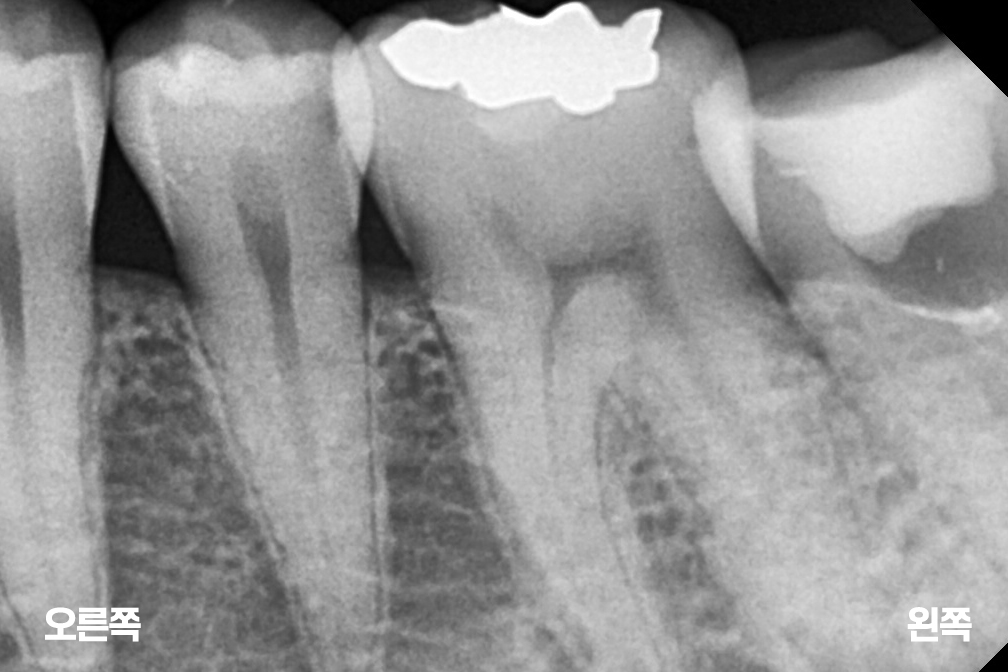

충치치료 왼쪽 아래 작은어금니(소구치) 충치치료

인레이

After 2025년 7월 15일